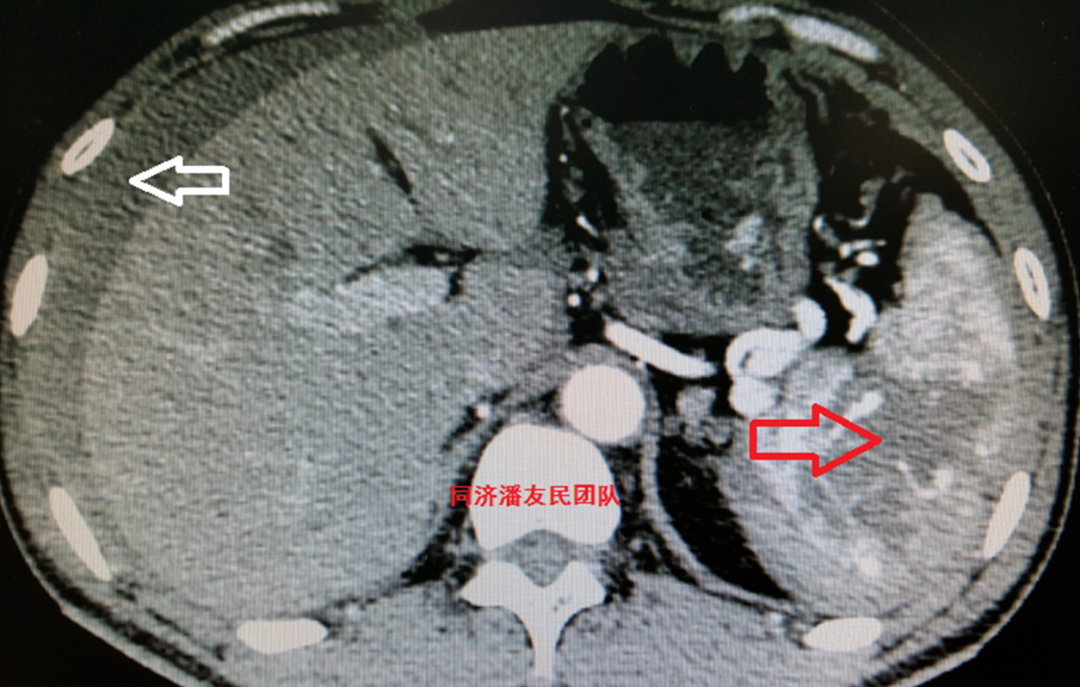

CTA同时发现脾脏破裂出血合并腹腔积液(图3)。

图3:红箭头显示脾破裂出血,白箭头显示腹腔积液。